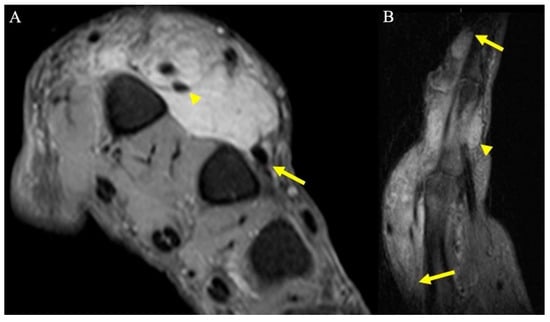

3. Soft-Tissue Malignancies

3.1. Clinical Features

3.2. Surgical Considerations